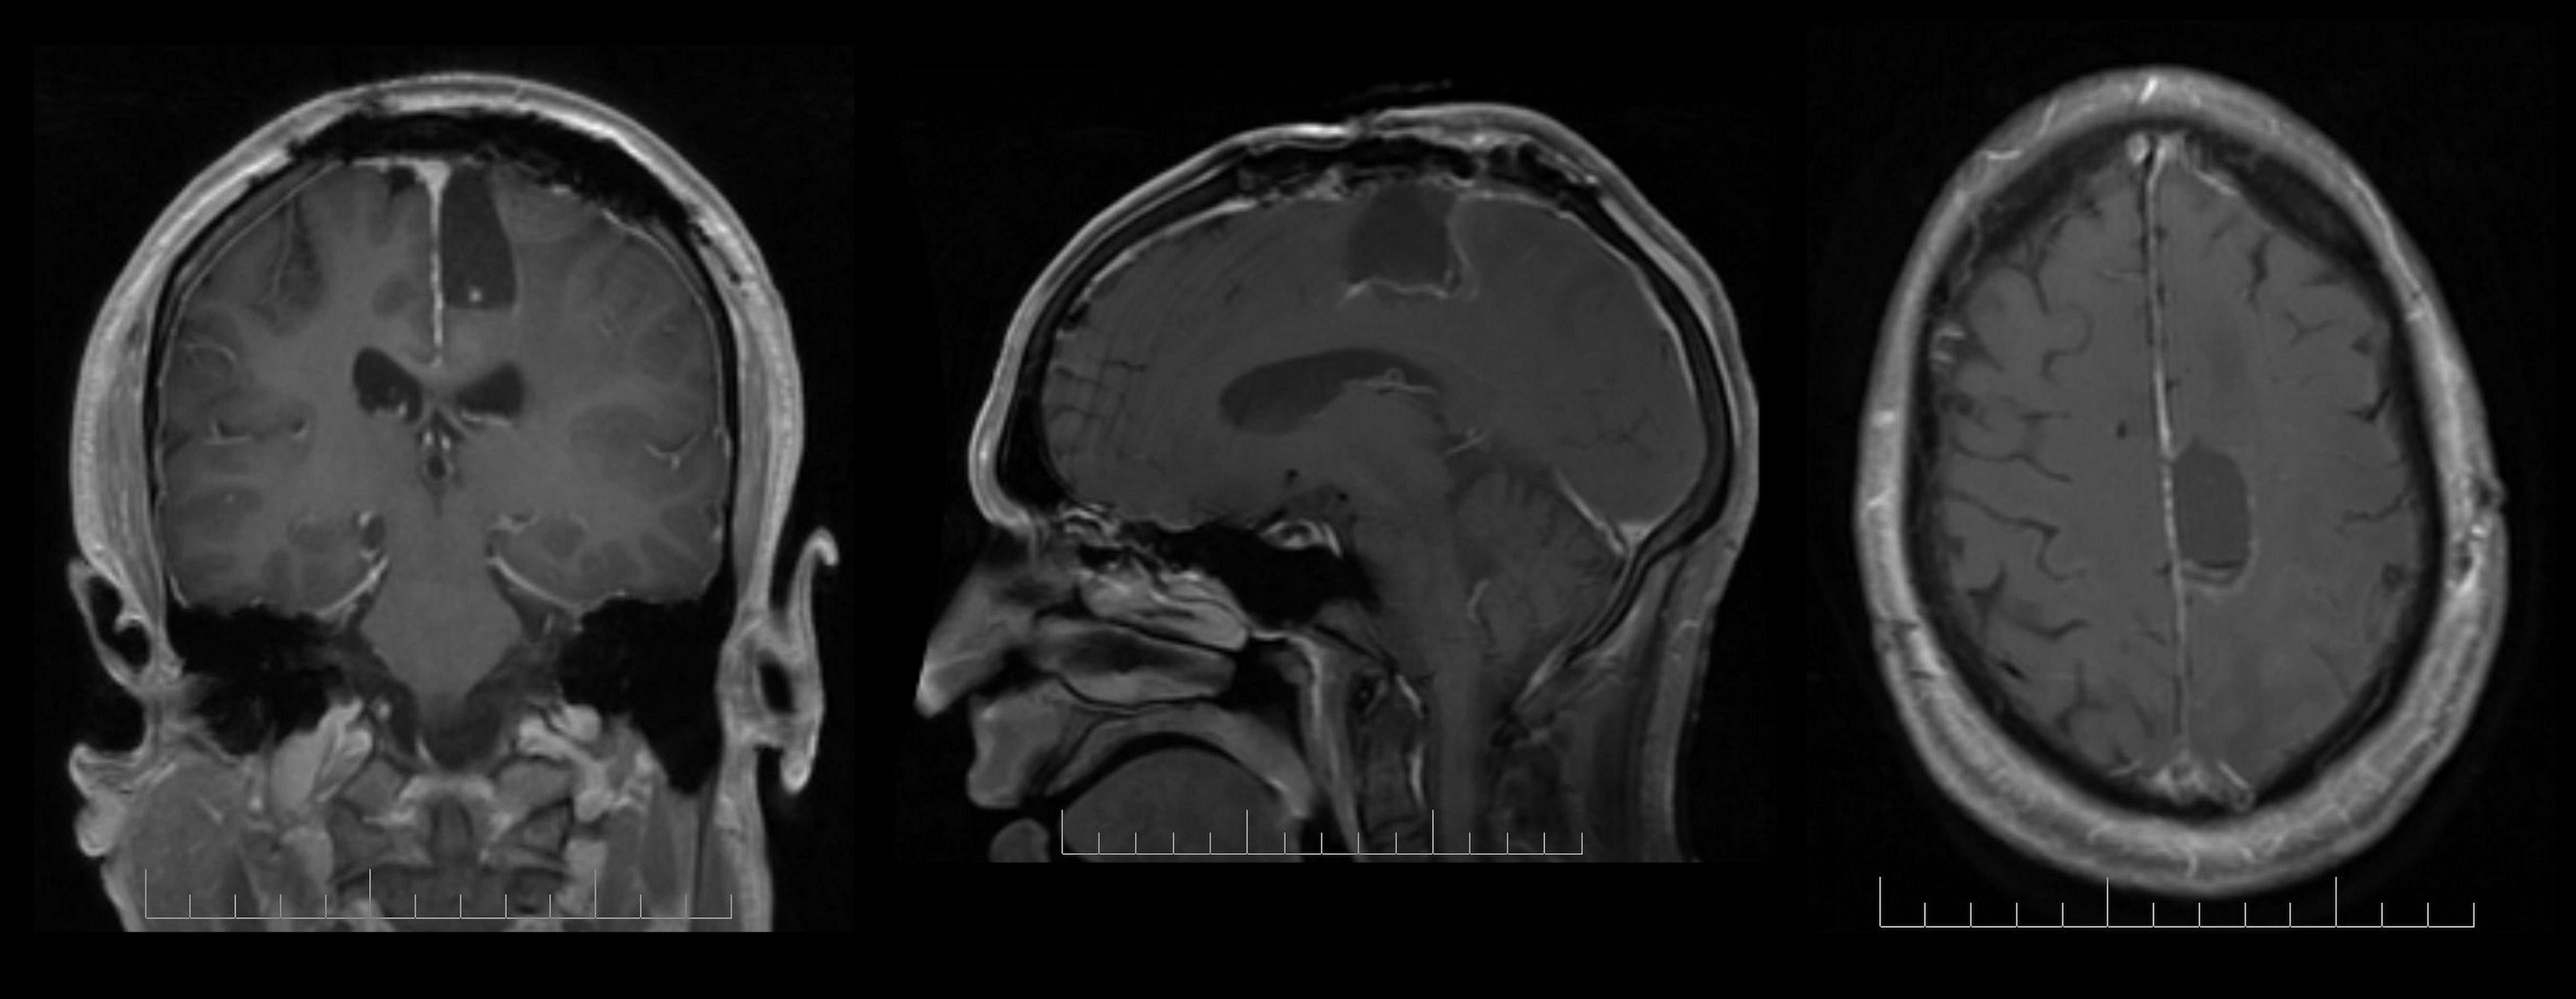

Although consistently associated with changes in grey matter, no prospective data have so far distinguished the differential effects of antipsychotic medication from psychosis progression in FEP. Sidhant Chopra, Monash University, Australia, presented the findings of a triple-blinded, placebo-controlled trial prospectively investigating changes in grey matter in medicated and non-medicated individuals following FEP.

Recruits aged 15-24 years of age received intensive psychosocial therapy and were given either an atypical antipsychotic or placebo for 6 months. Of the total 90 recruits, 62 (32 placebo; 30 active therapy) underwent neuroimaging at baseline, 3-months and 12-months as did a group of 27 healthy controls.

Over 12 months, low-dose atypical antipsychotic medication appeared to offer protective effects on the illness-related grey-matter decline seen within the hippocampus and supramarginal gyrus. Volumetric changes seen in the frontal pole, medial temporal, lateral occipital cortex and cerebellum were related to disease pathology, and appeared unaffected by low-dose medication. Greater volumetric increase within the supramarginal gyrus was associated with better symptomatic outcome, suggesting a key role for this region in mediating psychosis specific-symptomatic recovery.

Glutamine and glutamate levels were assessed using proton magnetic resonance spectroscopy in the anterior cingulate cortex (ACC) and the thalamus in 23 patients with FEP and in 15 healthy individuals at baseline, at 6 weeks and at 9 months. At 9 months, patients were classed as either remitters (n=12) and non-remitters (11).